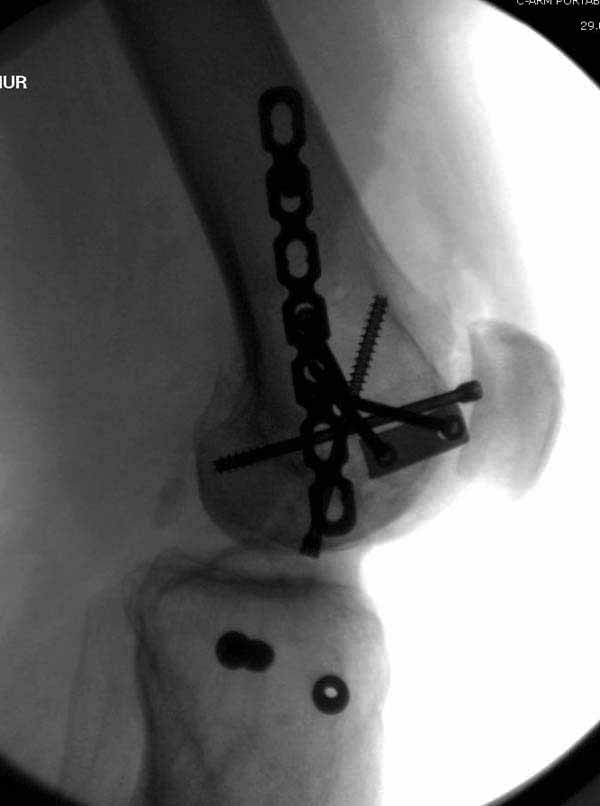

Коллеги, извиняюсь за задержку с результатом. Через медиальную артротомию обнажили н/3 бедра, отрепонировали внутренний мыщелок, затем по нему сопоставили суставную поверхность бедра с латеральным мыщелком.

Больная выписана в ортезе с регулируемым углом сгибания в колене, с рекомендациями через 3 нед. удалить спицы и начать разрабатывать сустав.

По прямому снимку репозиция удалось, поздравляю! А с латеральной стороны подозрение на флексионный компонент латерального мыщелка остается, а снимок получился косым, надо было бы повторить.

Выбор имплантов не совсем удачный, подкожно выступающие болты в мыщелках вскоре могут привести к проблемам. Вместо солитарной фиксации болтом-стяжкой дистально можно было бы добавить пару винтов, которые создали бы ротационную стабильность и межфрагментарную компрессию.

Возможно, есть скрытый замысел, неочевидный для нас - не понятны латерально оставленные спицы. Спицы возможный очаг вторичного осложнения, и, тем более у взрослых, тонкие спицы не создают адекватную фиксацию.

Djoldas,скрытого смысла в спицах нет. Без них латеральный мыщелок получается фиксированным только к медиальному, который, в свою очередь, фиксирован к проксимальному отломку. Соответственно латеральный мыщелок не фиксирован к бедру. Спицами мы попытались создать какую-никакую-стабильность латерального мыщелка относительно проксимального отломка бедра.

Болт-стяжка, на мой взгляд, создает не меньшую межфрагментарную компрессию чем винты. Не понял относительно ротационной стабильности винтов.